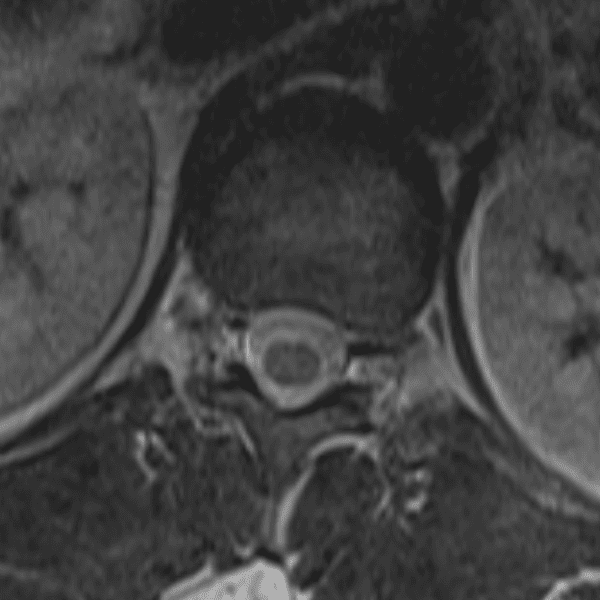

Simulates call by including subtle or difficult cases and some normals.

35 cases